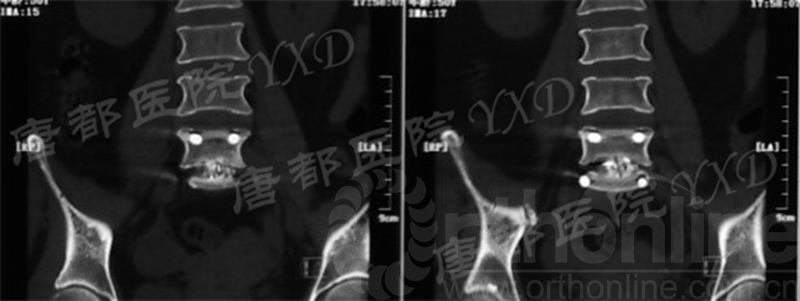

影像学检查:

诊断:腰椎间盘突出症术后复发

手术方案:显微镜辅助MI-TLIF腰椎翻修术

术中视频:http://api.orthonline.com.cn/attach/Case2.mp4(术中发现因前三次侧路及后路内镜手术的操作,术区大量瘢痕组织增生、与神经粘连严重;此外,摘除头侧游离髓核时连接有软骨终板脱落;在显微镜操作下,安全地将神经进行充分松解,压迫神经的游离髓核及软骨终板彻底清除。无手术并发症)

术后疗效:VAS评分左下肢1;左侧足背伸肌力、踇趾背伸肌力4级;左侧直腿抬高试验、加强试验阴性;行走自如、步态正常。